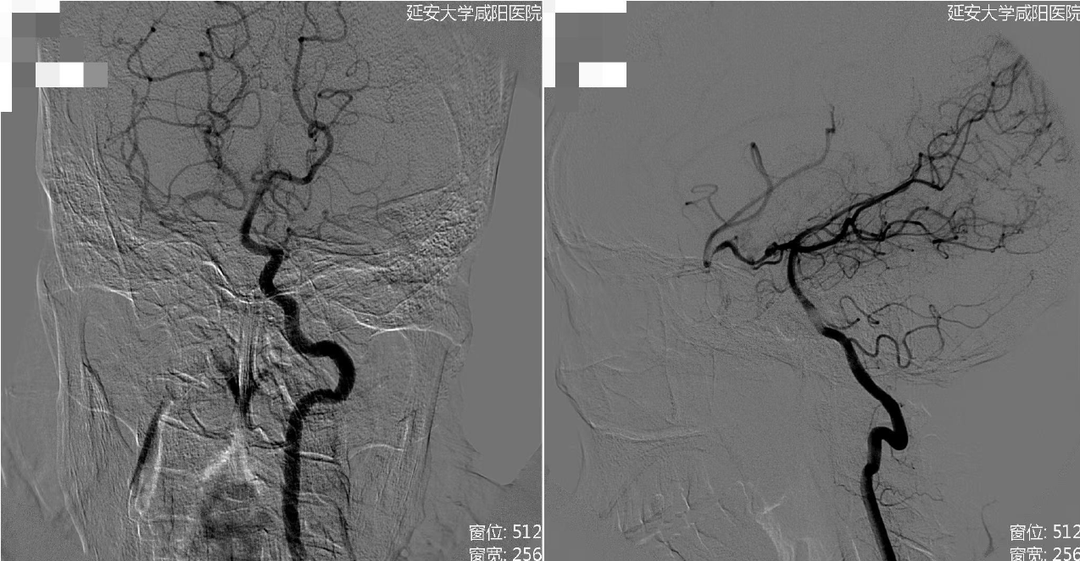

术前右侧椎动脉造影

术前左侧椎动脉造影

左侧颈总动脉造影

右侧颈总动脉造影